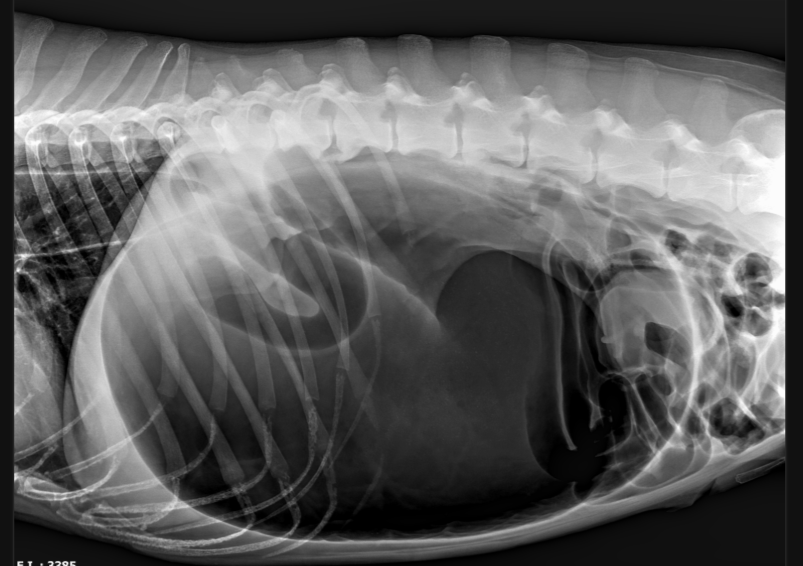

Diagnosing GDV in Dogs

Initial evaluation of a GDV patient commonly includes emergent abdominal x-rays (radiographs) and bloodwork. An ECG (electrocardiogram) will often be used to monitor your dog's heart for abnormalities since GDV progressively impacts the patient's circulatory system. The striking radiographic abnormalities often lead to a definitive diagnosis, so subsequent interventions can be taken immediately.